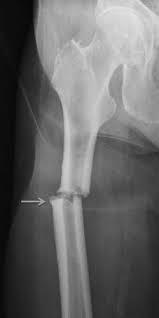

4th or 5th MCP

Bar room facture

2nd or 3rd MCP

fracture

Boxer’s fracture